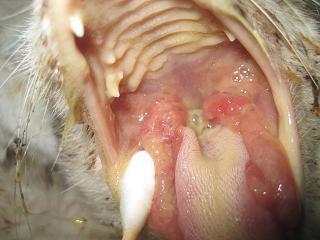

主題: 請幫助嚴重口炎 貧血 敗血 黃疸的貓咪 申請者姓名: 岳丹楓 花色: 申請日期: 2012-05-14 14:20:09 申請者部落格: 申請者臉書網址: 所在縣市/合作醫院: 台北市/詠欣動物醫院 治療費用: 12800元 需求人數: 16人 已結案 (2013-02-23 14:56:52) 報名人員: 波波(已付款)、黃寶妹(已付款)、廖靜郁(已付款)、Mia Chen(已付款)、Winnie Liu(已付款)、Celene Chu(已付款)、Hsing-hua Chang(已付款)、小嘟(已付款)、Keke Chien(已付款)、suxiwen(已付款)、suxiwen(已付款)、沛橙李(已付款)、HuaMing Sung(已付款)、Yiling Tsai(已付款)、劉靜怡(已付款)、Anita Yin(已付款)、 候補人員: Yuan-Hsin Kuo(已付款)、小舟、小舟、 動物病情說明: 這是平溪張媽媽從車輪下救回的貓咪,小時候撿到就有脫腸,緊急手術救回一條小命.最近,猛流口水和濃汁 不吃也不喝.經檢查發現有口炎黃疸 貧血和敗血. 經醫治目前狀況穩定 不流口水 食慾也非常好.已出院 繼續補鐵和吃抗生素. 謝謝大德們的幫助.